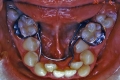

初診時